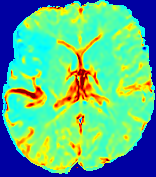

Slice #1Slice #2Slice #3Slice #4Slice #5Slice #6𝐕gt𝟐subscriptnormsuperscript𝐕gt2\|\bf{V}^{\text{gt}}\|_{2}Refer to captionRefer to captionRefer to captionRefer to captionRefer to captionRefer to caption𝐕est𝟐subscriptnormsuperscript𝐕est2\|\bf{V}^{\text{est}}\|_{2}Refer to captionRefer to captionRefer to captionRefer to captionRefer to captionRefer to captionRefer to caption1.51.51.51.21.21.20.90.90.90.60.60.60.30.30.30.00.00.0(mm/s)𝑚𝑚𝑠(mm/s)Destsuperscript𝐷estD^{\text{est}}Refer to captionRefer to captionRefer to captionRefer to captionRefer to captionRefer to captionRefer to caption0.0150.0150.0150.0120.0120.0120.0090.0090.0090.0060.0060.0060.0030.0030.0030.0000.0000.000(mm2/s)𝑚superscript𝑚2𝑠(mm^{2}/s)

Figure 14: PIANO identifiability testing: advection imaging via advection-diffusion. Top row shows 𝐕gt2subscriptnormsuperscript𝐕gt2\|{\bf{V}}^{\text{gt}}\|_{2} used for simulating ground truth pure advection. Rows below show the estimated 𝐕est2subscriptnormsuperscript𝐕est2\|{\bf{V}}^{\text{est}}\|_{2} and Destsuperscript𝐷estD^{\text{est}} on corresponding slices. Note that the plotted value scale for Destsuperscript𝐷estD^{\text{est}} is 0.01 of that for 𝐕gt2subscriptnormsuperscript𝐕gt2\|{\bf{V}}^{\text{gt}}\|_{2} and 𝐕est2subscriptnormsuperscript𝐕est2\|{\bf{V}}^{\text{est}}\|_{2}.

We use the same ‘Advection Imaging’ simulation of Sec. 4.2.1 as the concentration dataset for PIANO. However, instead of modeling pure advection (Eq. 15), we let PIANO estimate both velocity 𝐕estsuperscript𝐕est{\bf{V}}^{\text{est}} and diffusivity Destsuperscript𝐷estD^{\text{est}} via the advection-diffusion PDE (Eq. 2) underlying the proposed PIANO model. Fig. 14 shows the estimated 𝐕est2,subscriptnormsuperscript𝐕est2\|{\bf{V}}^{\text{est}}\|_{2}, and Destsuperscript𝐷estD^{\text{est}} fields for one patient. Although PIANO has the freedom to estimate both a velocity and a diffusivity field from pure advection, PIANO differentiates well between advection and diffusion: the estimated 𝐕est2subscriptnormsuperscript𝐕est2\|{\bf{V}}^{\text{est}}\|_{2} successfully reproduces the ground truth 𝐕gt2subscriptnormsuperscript𝐕gt2\|{\bf{V}}^{\text{gt}}\|_{2} governing the simulated advection process, just as it already did in the ‘Advection Imaging via Advection’ test (Fig. 12). More importantly, the estimated diffusivity Destsuperscript𝐷estD^{\text{est}} is orders of magnitudes smaller than 𝐕est2subscriptnormsuperscript𝐕est2\|{\bf{V}}^{\text{est}}\|_{2}, indicating the estimated diffusion is negligible compared to the estimated advection, which is highly consistent with the underlying pure advection of the simulated data.